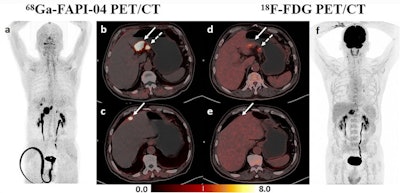

The authors reported that Ga-68 FAPI-04 PET/CT detected more primary lesions (90.3% vs. 77.4%, p = 0.008) and peritoneal metastases (91.7% vs. 41.7%, p = 0.031) and demonstrated higher SUVmax and TBR values (p < 0.001) of primary lesions compared to F-18 FDG PET/CT.

Dual-tracer PET/CT significantly improved the diagnostic sensitivity for the detection of distant metastases, compared with stand-alone F-18 FDG (97.1% vs. 73.5%, p = 0.008) or Ga-68 FAPI-04 (97.1% vs. 76.5%, p = 0.016) PET/CT.

Treatment strategies were then changed in nine patients following Ga-68 FAPI-04 and F-18 FDG dual-tracer PET/CT. Nevertheless, Ga-68 FAPI-04 uptake was primarily influenced by the size and invasion depth of the tumor. Both Ga-68 FAPI-04 and F-18 FDG PET/CT showed limited sensitivity for detecting early gastric cancer (37.5% vs. 25%, p > 0.05).